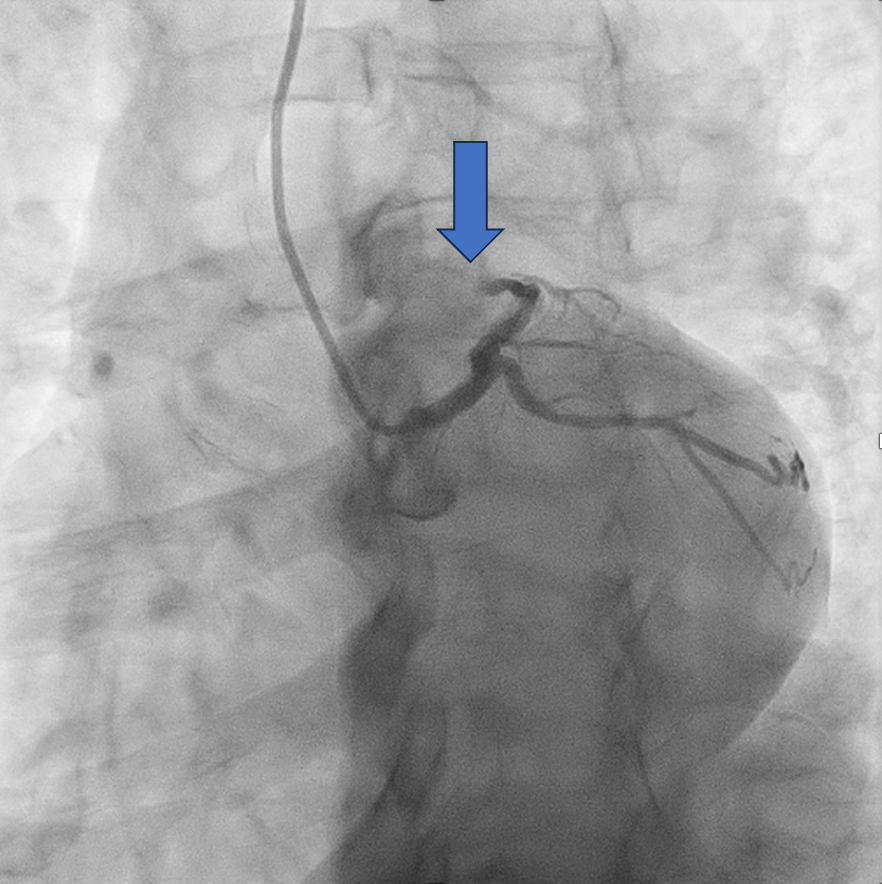

CORONARY ANGIOGRAM REVEALED CHRONIC TOTAL OCCLUSION AT THE MID LEFT ANTERIOR DESCENDING ARTERY (MLAD) WITH COLLATERALS FROM RIGHT CORONARY ARTERY. OTHER CORONARIES ARE NORMAL.

WE DECIDED TO INTERVENE THE CTO MLAD IN VIEW PERSISTENT ANGINA. BILATERAL RADIAL ARTERY PUNCTURE, WITH ANTEGRADE APPROACH. WE ENGAGED RIGHT CORONARY ARTERY WITH JR4 6 FR AND WIRED DOWN WITH RUNTHROUGH FLOPPY. ENGAGED THE LEFT CORONARY ARTERY WITH EBU 3.5 7FR. INITIALLY TRIED TO WIRE THE LAD WITH FINECROSS MICROCATHER (MC) USING SION BLACK WIRE BUT FAILED. SUBSEQUENTLY CHANGED TO GAIA 1ST AND MANAGED TO CROSS SUCCESSFULLY. IVUS SHOWED 360 DEGREE CALCIFICATION WITH 270 DEGREE CALCIFICATION MORE THAN 5 MM, IVUS CALCIUM SCORE 2. CALCIUM DEBULKING WAS DONE USING ROTABLATION WITH 1.5 BURR RUN 3 TIMES AT 220 KRPM FOR 10 SECS AND POLISHING RUN TWICE AT 140 KRPM. POST ROTA SHOWED PRESENCE OF FRACTURED CALCIUM WITH REVEBERATION SIGN. LESIONS WAS PREPARED FURTHER USING WOLVERINE 3.0 X 10MM AND 3.5 X 10MM. POST CUTTING BALLOON SHOT SHOWED NO DISSECTION, TIMI 3 FLOW AND RESIDUAL STENOSIS 30%. DECIDED FOR DCB WITH PANTERA LUX 3.0 X 20MM AND AGENT 3.50 X 30MM. FINAL SHOT SHOWED TIMI3 FLOW, NO DISSECTION SEEN. PATIENT REMAIN ASYMPTOMATIC AT 6 MONTHS AND REPEATED COROS SHOWED MODERATE STENOSIS AT MLAD WITH NEGATIVE FFR (0.92).